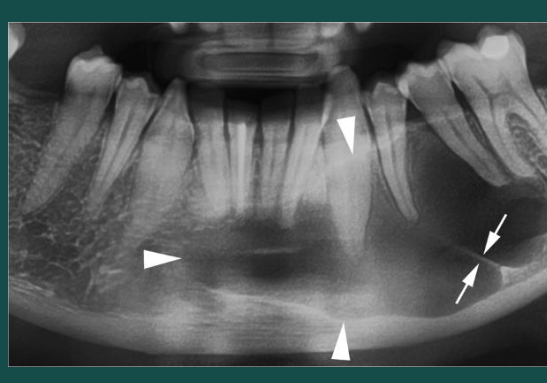

Osteomyelitis

malignancy

moth eaten destructive RL

Osteosarcoma

Mixed

sunburst RO

widening PDL space without trauma

irregular destructive bone changes

pain and swelling clinically

malignant